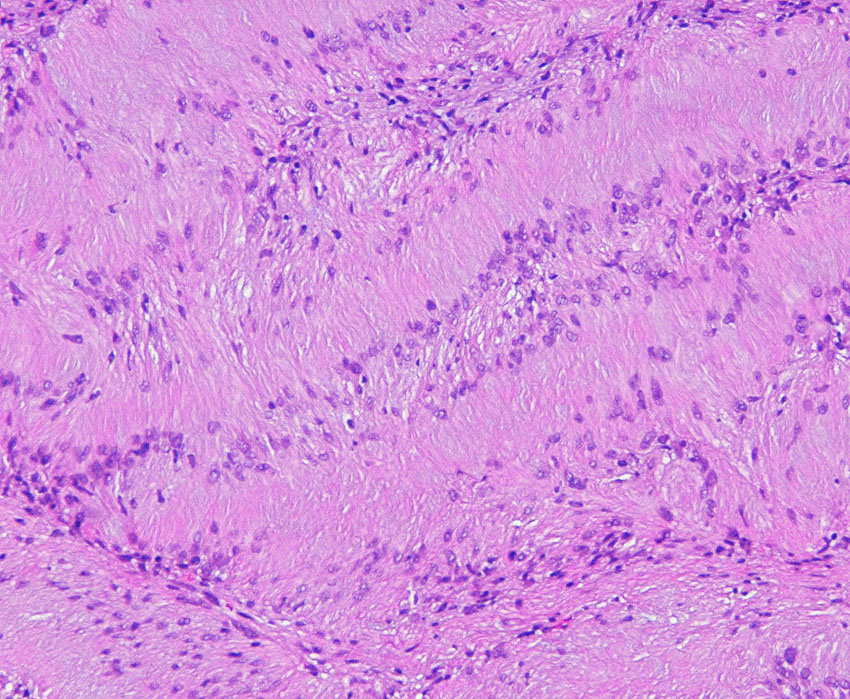

腫瘍細胞はS-100蛋白の免疫染色で陽性を示します。細胞密度が高くnuclear palisadingを示すAntoni type Aの部位(長い矢印)と細胞が比較的粗に配列するAntoni type Bの部位(短い矢印)でも陽性となります。S-100 x100.

紡錐型の核を有する腫瘍細胞で構成されます。左側の写真のように,古典的病理所見として,束状 fascicular に配列する密な組織である Antoni A Typeと網状 reticular で疎な組織である Antoni B Typeが混在するパターンを示します。神経鞘腫では多少の核の異型性がみられても悪性像とはいえません。嚢胞を形成したり,時には毛細血管拡張 simple hemangioma を思わせるような著明な血管の増生があり腫瘍内出血をきたすことがあります。